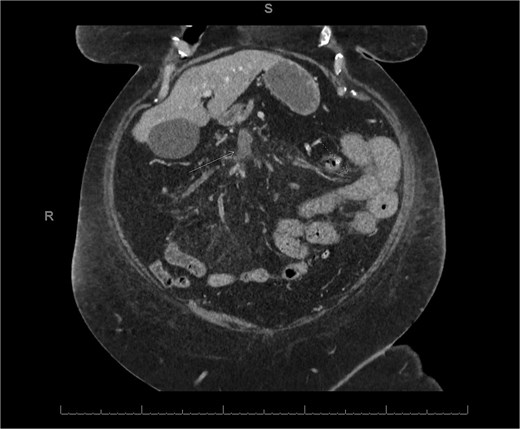

A 76-year-old female with a 3-day history of left upper abdominal pain, vomiting, and haematochezia. Her history included pulmonary embolism, multiple deep vein thromboses, with no ongoing anticoagulation, and an open partial colectomy for complicated diverticulitis a decade earlier. On admission, she was afebrile but tachycardic and showed localized tenderness in the left hypochondrium. Laboratory revealed leucocytosis with a white blood cell count (WBC) of 12 G/L, elevated C-reactive protein (CRP) of 46 mg/L, and hyperlactatemia of 2.6 mmol/l. Enhanced computed tomography (E-CT) revealed jejunal venous ischemia in the left upper quadrant, secondary to extensive porto-mesenteric thrombosis with reduced bowel wall enhancement, distention, and free intraperitoneal fluid (Fig. 1). She was managed conservatively with unfractionated heparin (UFH) with a bolus of 5000 U/l followed by 30 000 U/l/24 h (target INR 0.35–0.7), Piperacillin-Tazobactam, and bowel rest. After 48 h of monitoring in the intensive care unit (ICU), she exhibited marked biological and clinical improvement. E-CT on the third day showed restored bowel wall enhancement and stable porto-mesenteric thrombosis (Fig. 2). She was discharged on therapeutic low molecular weight heparin (LMWH) with enoxaparin sodium 120 mg every 12 h. At the 3-month follow-up, E-CT revealed near-complete thrombus resolution, without intestinal sequelae (Fig. 3).

Abdominal E-CT of the first patient at admission. The white arrows indicate extended porto-mesenteric thrombosis, while the dashed arrows reveal jejunal venous ischemia with a lack of bowel wall enhancement, bowel distension, and free fluid.